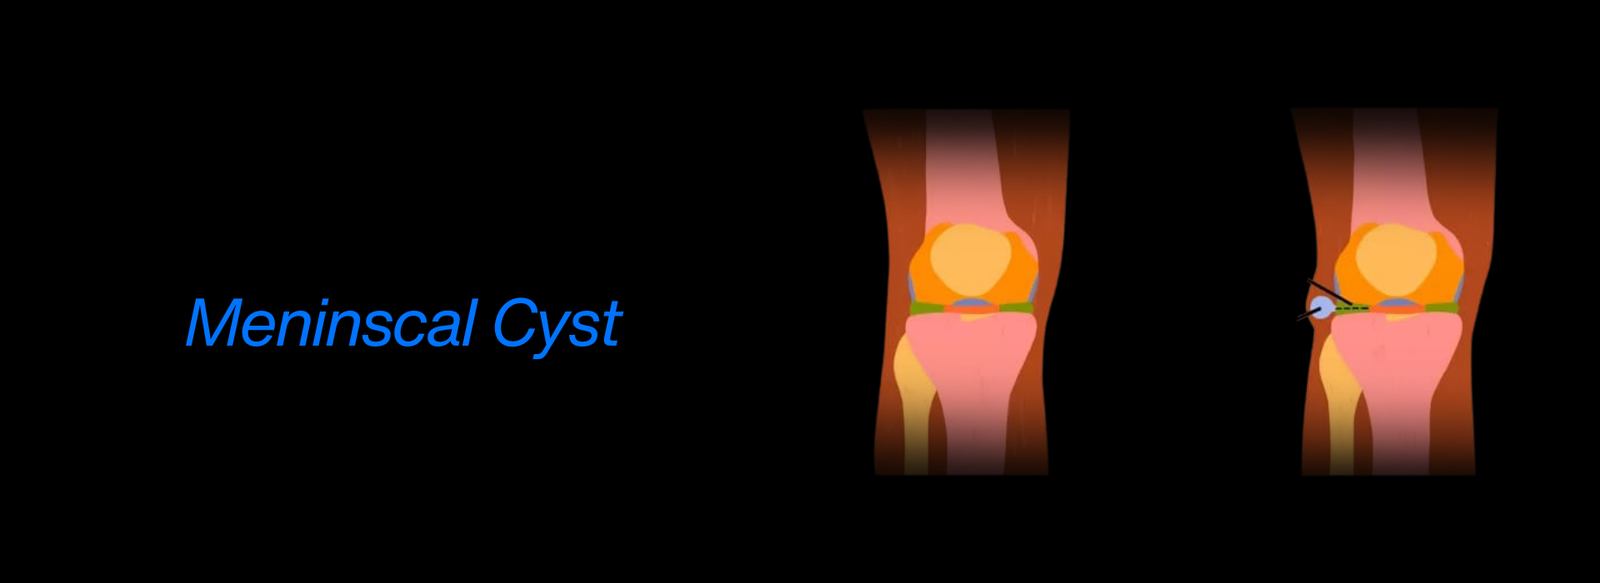

Fellowship in Arthroscopy: Expertise in minimally invasive surgery to diagnose and treat joint conditions, such as torn cartilage or ligament injuries, particularly of the knee, shoulder, and hip.